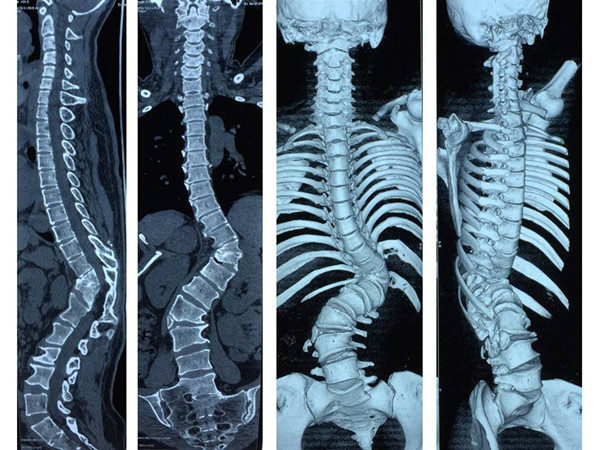

术前全脊柱CT三维重建

来自我省咸阳市的患者张某,因胸腰部脊柱畸形30余年,腰部疼痛1月慕名来我院求诊。患者为成年女性,诊断为先天性脊柱侧弯。病程长,儿时有过手术史,侧弯Cobb角度超过90度。入院后科内反复讨论,研读患者的影像学资料,并采用3D打印重现患者脊柱骨性结构(1:1)。在此基础上,制定了详细的术前计划及整体治疗方案。治疗过程中,采取骨性牵引2周,缓解手术矫形时神经肌肉血管的张力,降低手术风险,手术当天,由贺西京教授主刀,李浩鹏教授,王栋副教授,赵波、秦杰主治医师、王放住院总医师密切配合,在麻醉科及手术室的协助下,施行截骨矫形手术。术中诱发电位监护、自体血回输,唤醒试验、中心静脉压、外周动脉压监护、保温毯等措施保护患者的生命安全及神经功能。患者畸形严重,手术非常复杂,稍有不慎即有可能导致瘫痪,给患者和家属带来严重负担。贺西京教授、李浩鹏教授、王栋副教授等手术麻醉人员全神贯注,一丝不苟,连续手术8小时,患者脊柱畸形明显纠正,侧凸Cobb角纠正至20°,生命体征及神经功能完好,患者截骨矫形手术顺利完成。术后在我科护理和我院康复科医师的精心护理康复下,患者1周下地站立行走,顺利康复。术后无明显并发症,患者及家属对手术效果非常满意,现已出院。